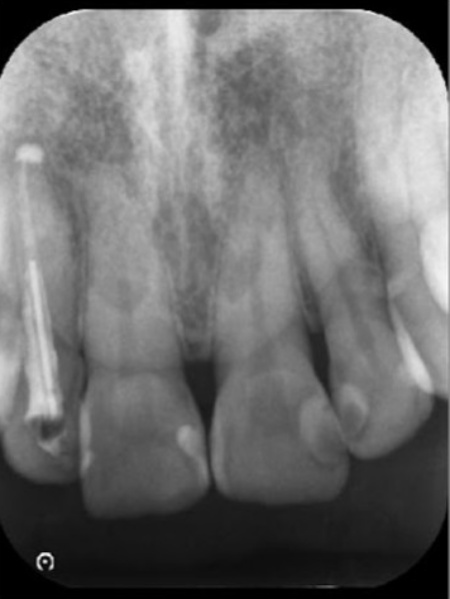

治療終了から2年後のレントゲン画像です。根尖病巣が改善しています。

レントゲン検査を行って詳しく調べた結果、歯の根の先に歯の頭と同程度の大きさの根尖病巣(こんせんびょうそう)が確認できました。

根尖病巣とは歯の根の先にできる膿の袋のような病変です。

歯の内部の神経や血管が通る細い管に細菌感染が起こり、その影響が根の先に広がることで生じます。